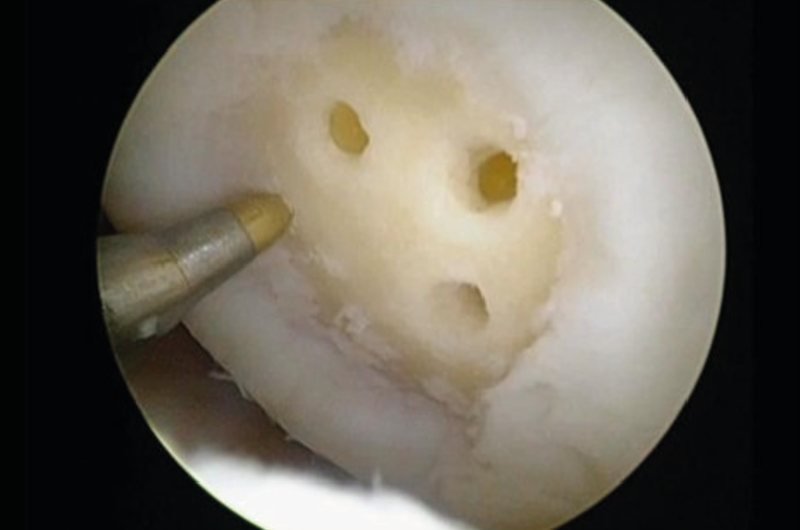

In practice, care must be taken to clean up the subchondral calcifying layer without grossly damaging the subchondral lamella (Fig. 12).

If possible, the use of finer grade reamers called “nano fracturing”, (Fig. 13) or low-speed microdrilling (Fig. 14) with K-wires (1.0−1.6 mm) should be favoured.

The common larger chondro picks tend to result in confluent fine subchondral fractures and increase the risk of intralesional osteophyte formation (Fig. 15) and subchondral cyst formation.